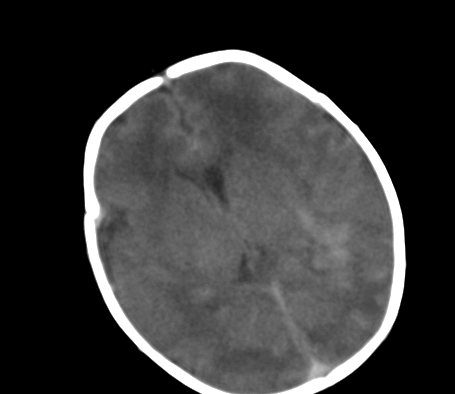

标题: PED0831:患儿,5天,是HIE吗?

患儿,出生时正常,第5天突然呕吐两次,无发热及抽搐。

片示:双侧大脑半球脑实质密度降低,皮髓分界尚清,左侧顶部脑沟内见铸形高密度影,脑中线结构居中。

2、hie并少量蛛网膜下腔出血。

hie !看皮质很薄是否早产?